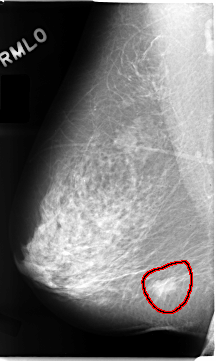

FILE: C_0102_1.RIGHT_MLO.OVERLAY

TOTAL_ABNORMALITIES 1

ABNORMALITY 1

LESION_TYPE MASS SHAPE IRREGULAR MARGINS SPICULATED

ASSESSMENT 5

SUBTLETY 5

PATHOLOGY MALIGNANT

TOTAL_OUTLINES 1

BOUNDARY